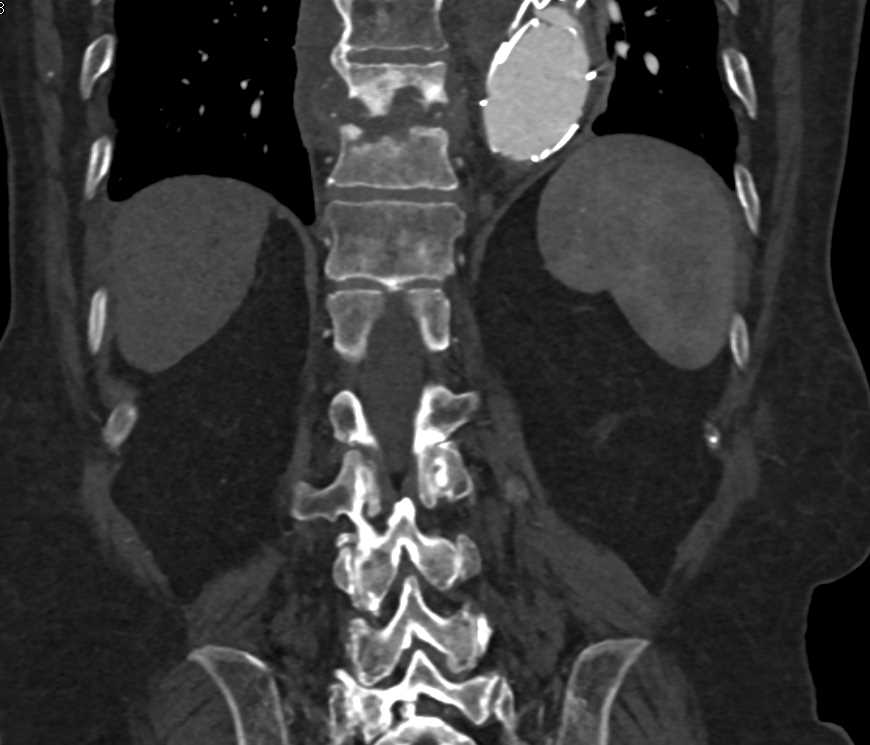

Lymphoma with Adrenal and Liver ad Lung Involvement